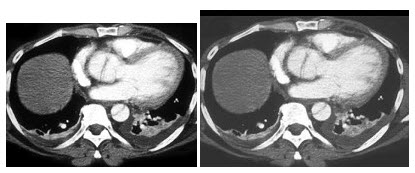

18、单项选择题

男,73岁,呼吸急促半天,CT扫描如图,正确的描述或诊断是()

A.冠状动脉壁可见钙化影,右侧明显

B.右侧冠状动脉局限性梭形扩张

C.心包肥厚

D.右侧冠状动脉瘤

E.左侧冠状动脉瘤